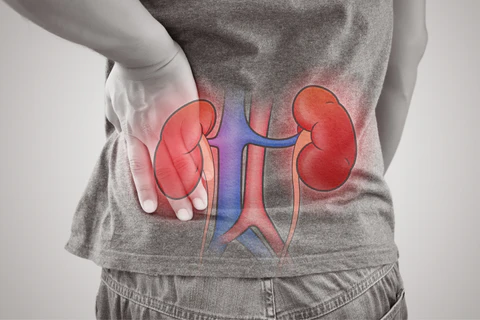

Mereka yang mempunyai keturunan pernah menderita gout juga berisiko tinggi untuk mendapat sakit gout suatu hari nanti. Ini bukan disebabkan oleh masalah asid urik lagi tetapi disebabkan “genetic variants” yang mana menyebabkan buah pinggang tidak dapat keluarkan asid urik dengan sempurna. Secara umumnya gout ini dikaitkan dengan artritis iaitu radang pada sendi.

Jawapannya adalah tidak. Ia akan menyebabkan terjadinya masalah batu karang pada buah pinggang yang juga amat sakit. Disebabkan itulah pesakit gout dinasihatkan untuk minum air putih yang banyak untuk mengelakkan daripada terjadinya masalah batu karang.

Masalah batu karang pada buah pinggang boleh terjadi komplikasi dari gout yang tidak dikawal dengan baik.

i) Obes / gemuk / lebih berat badan. Individu ini mempunyai risiko 4 kali ganda lebih tinggi untuk mendapat sakit gout berbanding individu normal. Mereka juga terdedah dengan risiko masalah metabolik. Individu yang mengalami masalah buah pinggang dan masalah hormon seperti hipo paratiroid juga terdedah kepada risiko gout.